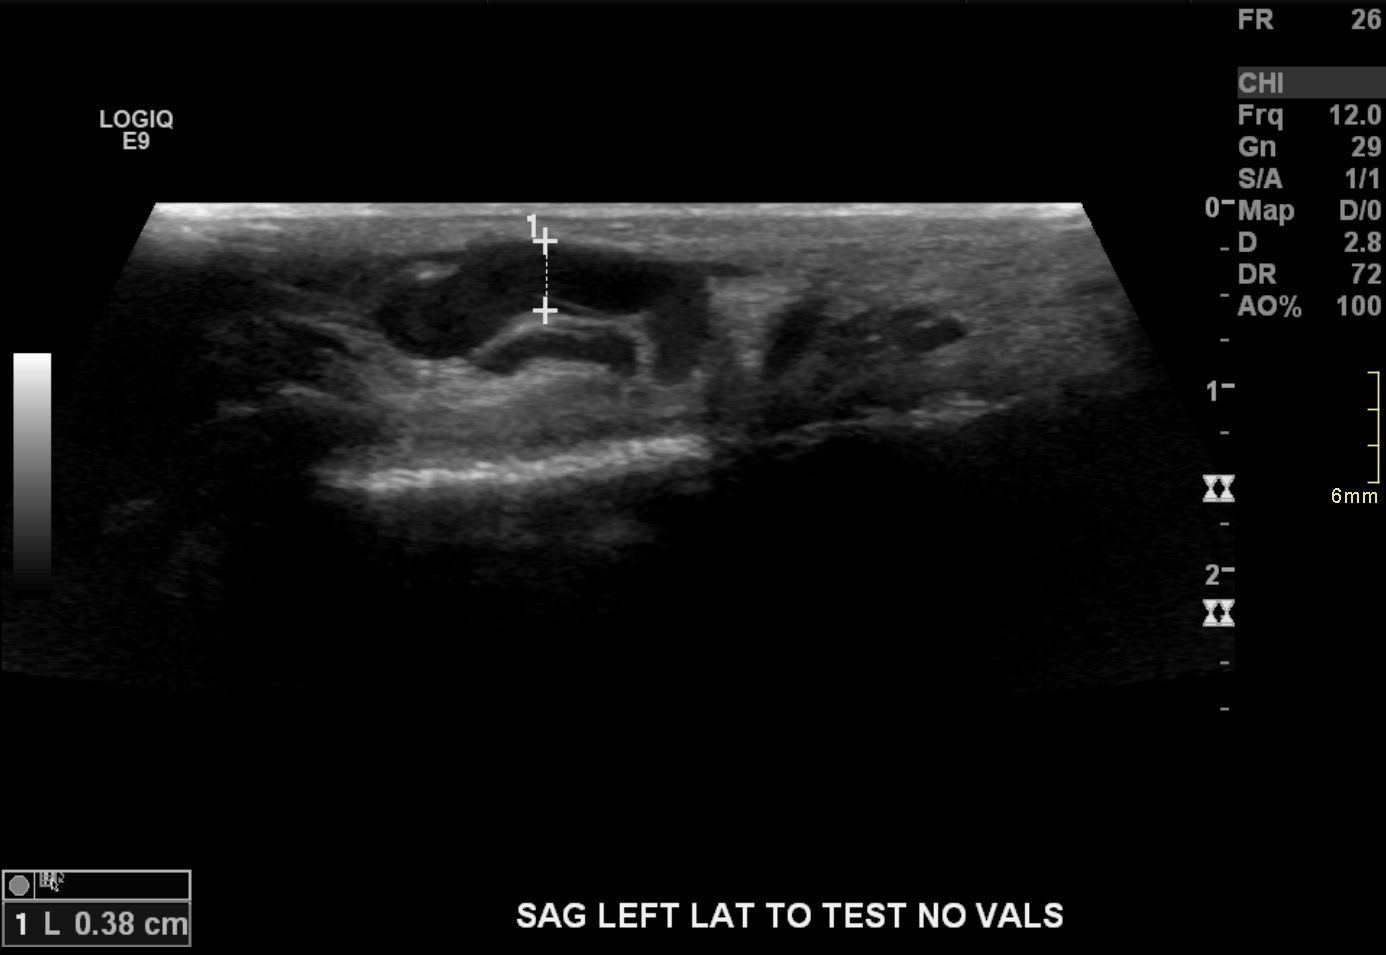

17-year-old male with a long history of left-sided varicoceles status post surgical ligation in 2015 presents with recurrence of symptoms, referred to us for left gonadal vein embolization.

Ultrasound demonstrates enlarged veins (>3 mm) adjacent to the testicle. Angiogram demonstrates reflux of contrast into the left gonadal vein to the level of the scrotum, indicating venous valvular incompetence. Coil embolization and sotradecol sclerotherapy of the left gonadal vein were performed, with an Amplatzer plug at the top of the vein. Repeat angiogram demonstrates no contrast opacification of the vein. Red arrows indicate the left gonadal vein and the blue arrows indicate the left renal vein.

The patient's symptoms have resolved.

Aaron Harmon, MD, Assistant Professor, Interventional Radiology